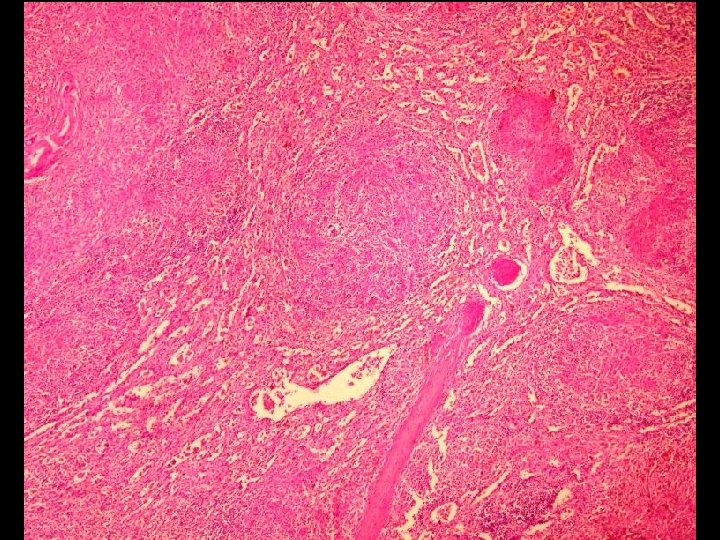

Caso 1 • Paciente masculino de 70 años, historia de dorsalgia que no responde

Caso 1 • Paciente masculino de 70 años, historia de dorsalgia que no responde a analgésicos, se agrega insuficiencia cardiaca. • Radiología de columna demuestra focos de destrucción ósea múltiples en cuerpos vertebrales. • Fallece por cuadro de descompensación cardiaca, en autopsia se confirma lesiones líticas de columna. • Se presenta histología y pesquisa de cadenas de inmunoglobulinas en foco lítico.